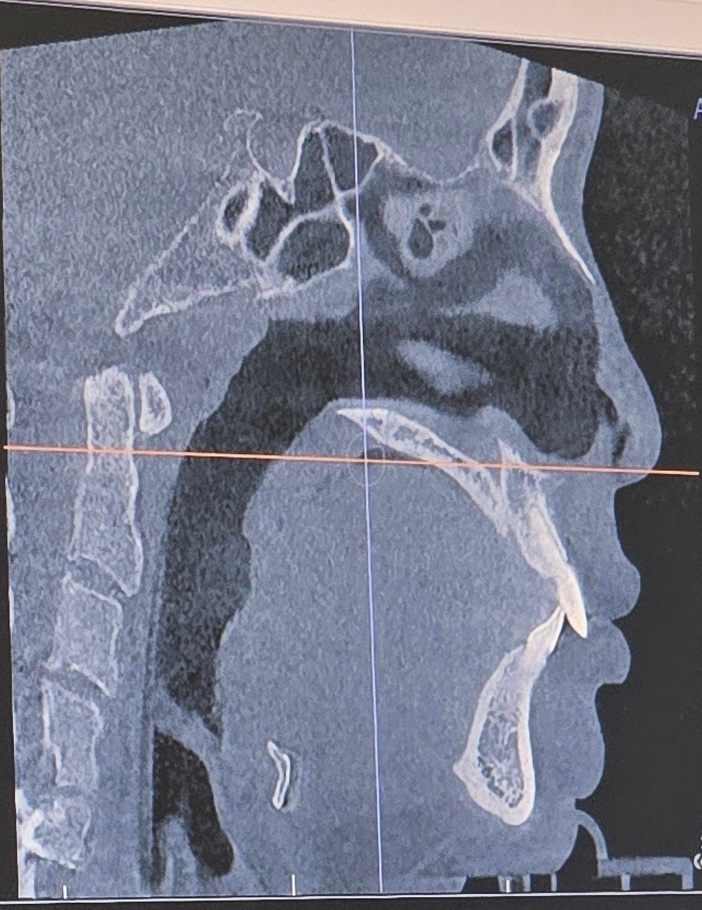

코는 어디까지 건들지가 관건인데

일단 내가 당장 거슬리는건 콧대가 매우 낮은게 아니라 없는 수준인점이라

콧대는 실리콘 코끝은 귀연골쓰고 콧볼축소 하고.. 이정도만 생각중

매부리는 잘 모르겠다.. 같이 하는게 나으려나?

1월에 검사, 상담 받았을때 사진 같이 첨부할테니 조언 해줄 사람 있으면 좋을듯!